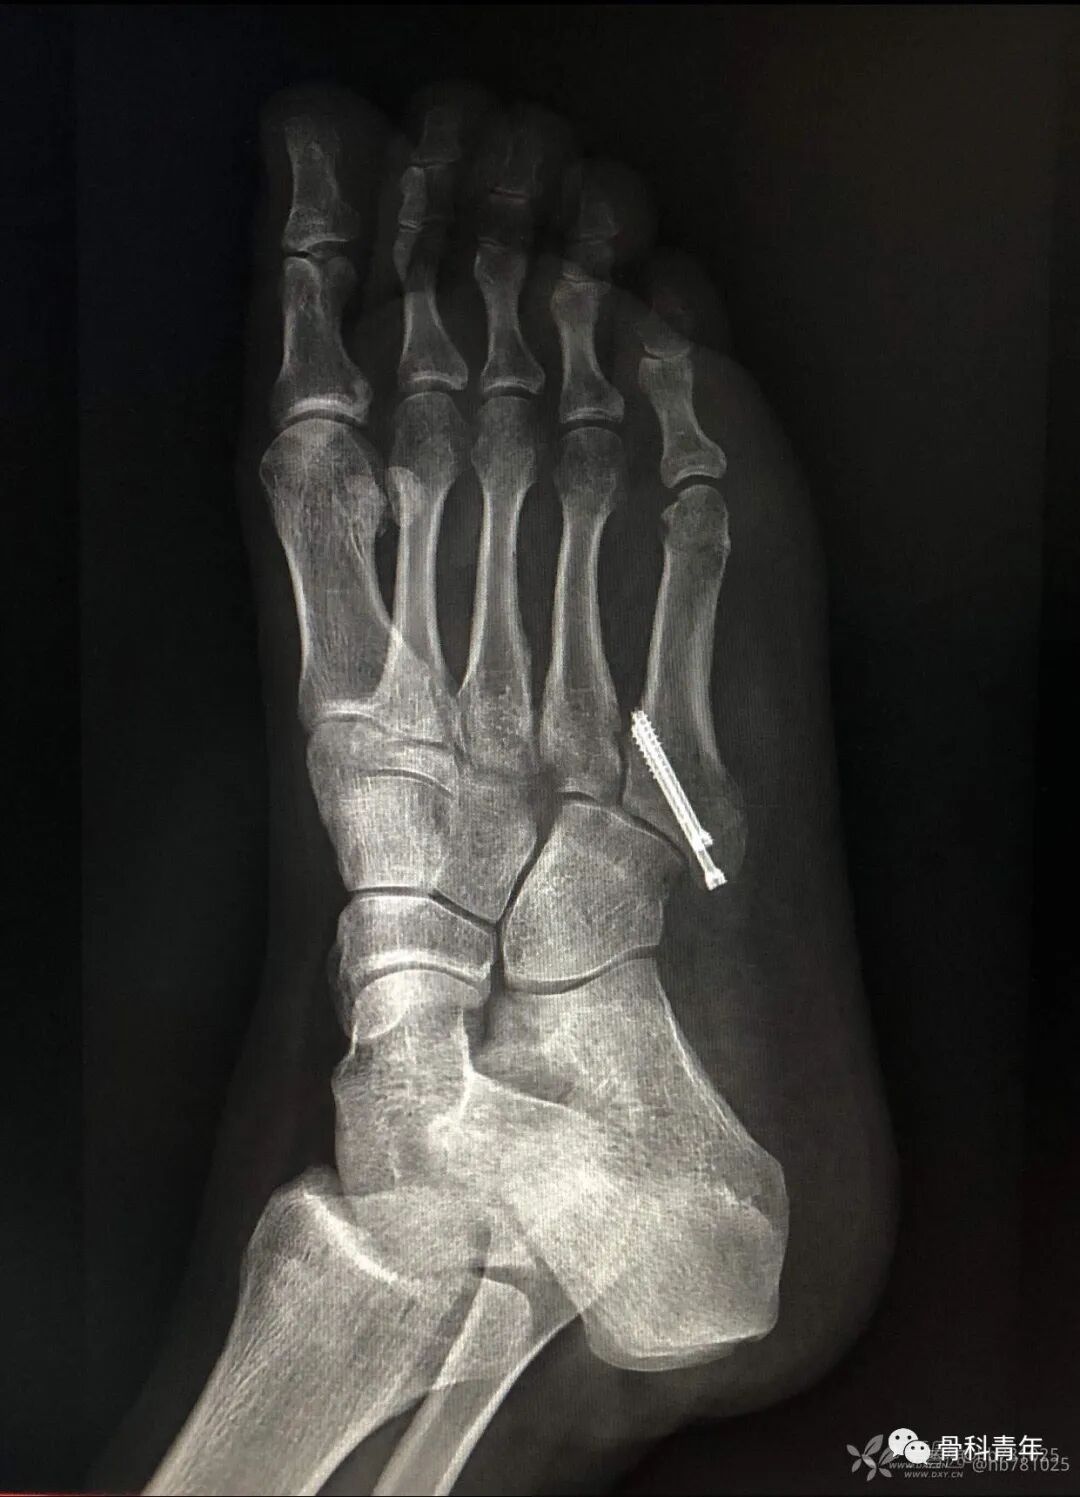

16.第五跖骨基底部骨折(空心钉)